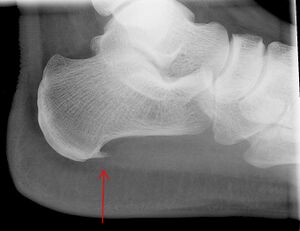

النتيجة العرضية المرتبطة بهذه الحالة هي مهماز العقب، تكلس عظمي صغير على العقب (عظم الكعب)، الذي يتواجد في حوالي إلى 50٪ من المصابين بالتهاب اللفافة الأخمصية.[6] في مثل هذه الحالات، فإن التهاب اللفافة الأخمصية هو الذي يسبب ألم العقب، وليس المهماز نفسه.[13] الحالة هي المسؤولة عن تكوين المهماز على الرغم من أن الأهمية السريرية لمهماز العقب في التهاب اللفافة الأخمصية لا تزال غير واضحة.[12]

لا توجد حاجة روتينية للتصوير الطبي. فهو مكلف ولا يغير عادة كيفية علاج التهاب اللفافة الأخمصية.[15] عندما لا يكون التشخيص واضحًا من الناحية السريرية، فإن الأشعة السينية للرؤية الجانبية للكاحل هي طريقة التصوير الموصى بها لتقييم الأسباب الأخرى لألم الكعب، مثل كسور الإجهاد أو تطور مهماز العقب.[7]